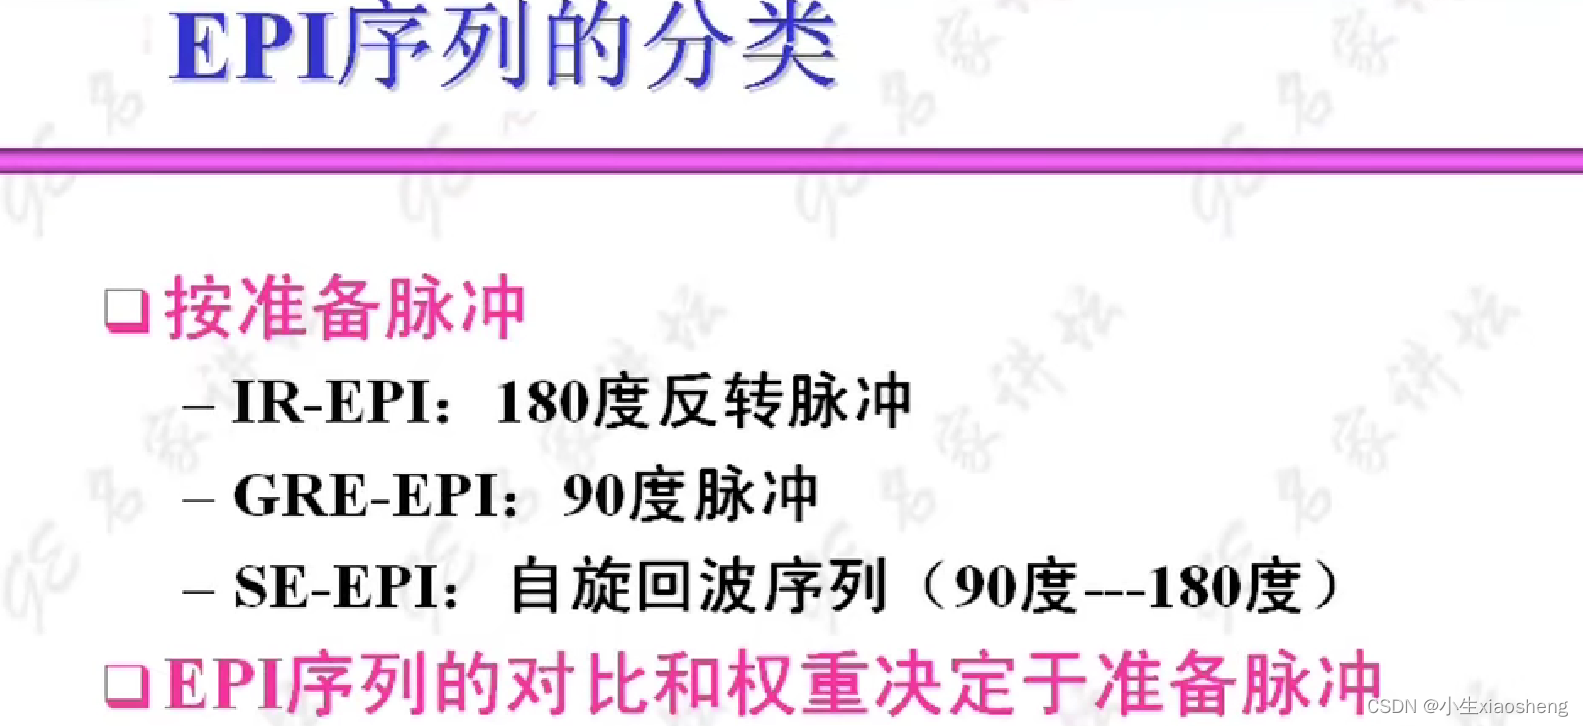

自旋回波--90度和180度填充K空间;反转恢复--在自旋的基础上两边加180度;梯度回波--消除每次脉冲留下的影响,以及波的次数;propeller==》K空间填充技术和FSE或FIR结合用于减少运行伪影;EPI==》采集方式,一次激发采集多个回波的形式但与单次不一样;PRESTO和GRASE==》前面几种的一种结合形成新的。

七、EPI序列

当然连续时不会像单次激发那样把整个K空间填满,还是需要经过几个90度脉冲。